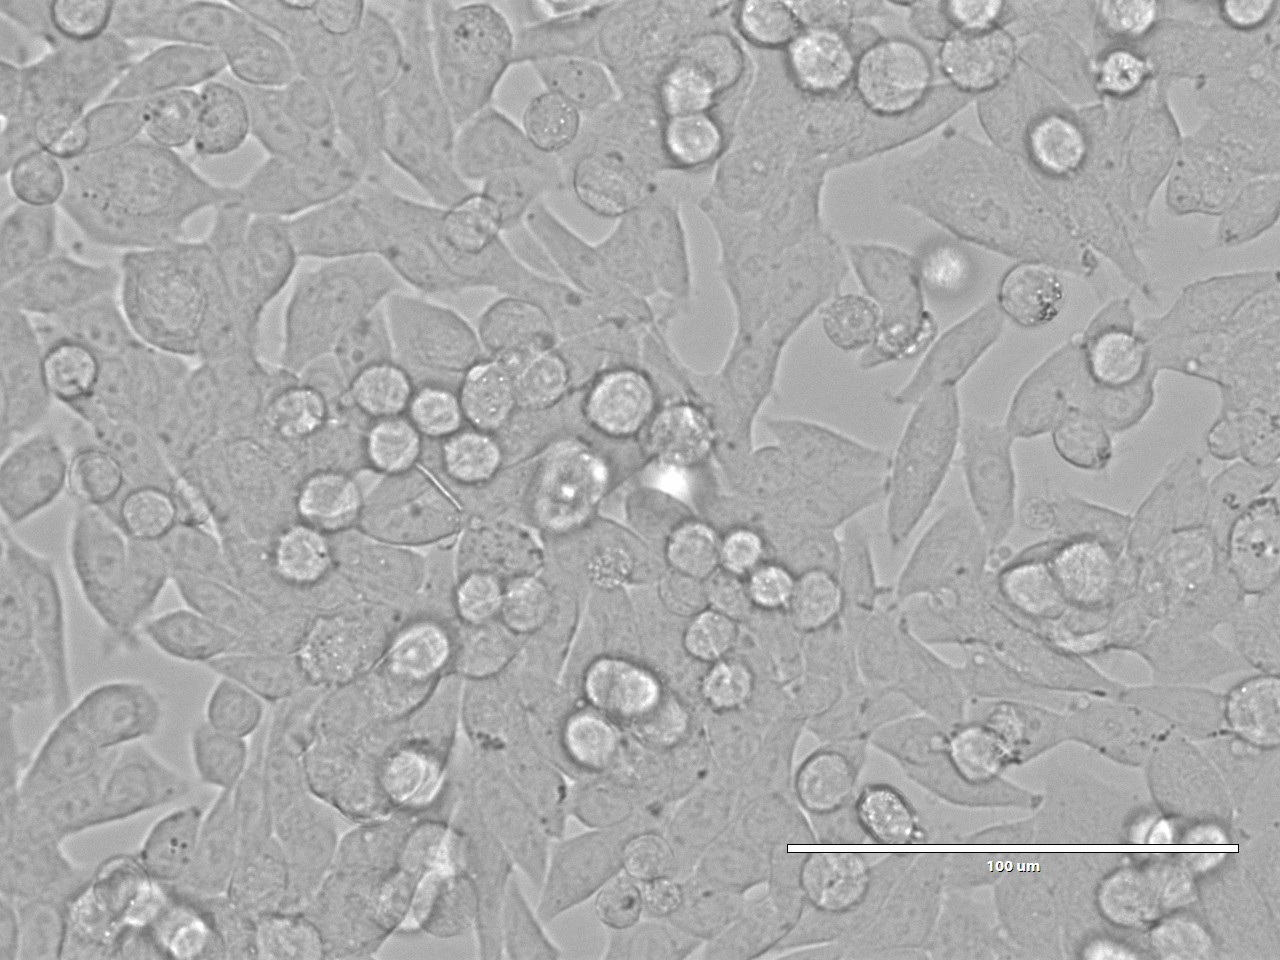

SW620(人结直肠腺癌细胞)细胞从一个51岁男性白人组织中分离得到,由A.Leibovitz等从一个淋巴结建株。细胞系主要由无绒毛的小圆球细胞和双极细胞组成。它仅合成少量癌胚抗原(CEA)且在裸鼠中有高度的致瘤性。